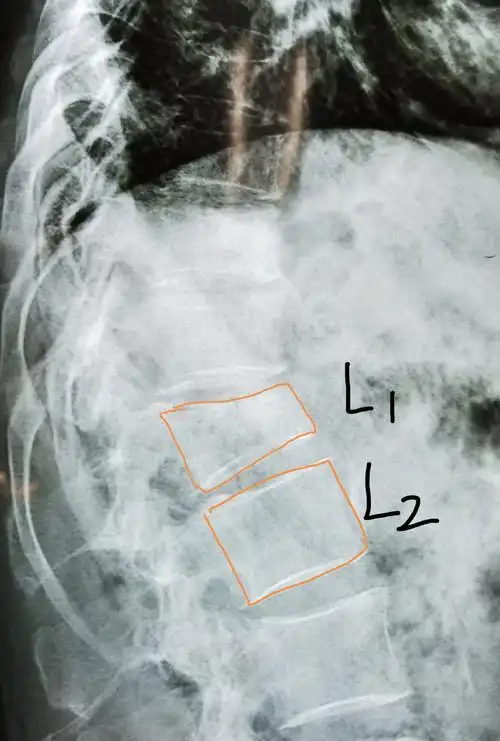

腰1椎体压缩骨折复位固定

腰1椎体压缩性骨折(3度)

腰椎平片提示腰1椎体前缘压缩有二分之一,侧位片非常明显,且腰椎ct

38床, 腰1椎体压缩性骨折